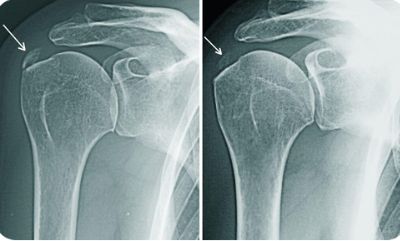

- Чтобы выявить перелом, назначают рентгенографию плечевого сустава.

- Диагностика включает в себя рентгенографию, МРТ и клинические анализы.

- Диагностика проводится с помощью рентгенографии пораженного сустава и клинических анализов крови.

- Диагностика проводится с помощью рентгенографии, а также осмотра доктора.

- Диагностика проводится с помощью диагностических тестов, дополнительно может быть назначен рентген.